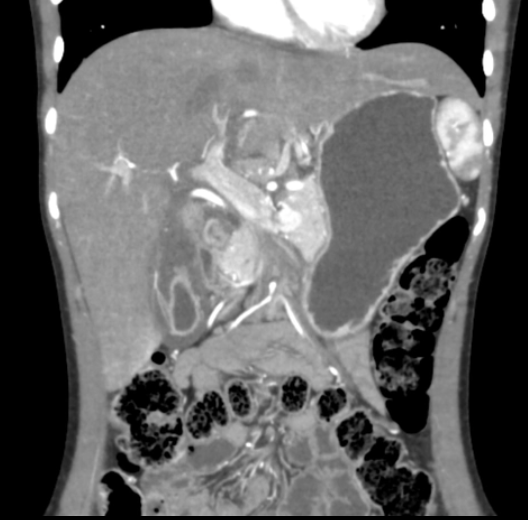

Hepatic infection: abscess

Px: most common general cause; common causes; less common cause; most common organism.

Ix: CT-1

Px: bowel process; diverticulitis, appendicitis; ascending cholangitis; E. coli.

Ix: CT: ring-enhancing lesion